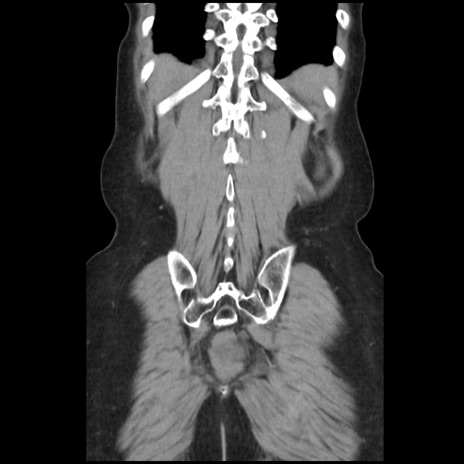

症例32(冠状断像)

【症例】40歳代 女性

【主訴】上腹部痛、嘔気・嘔吐

【現病歴】約9時間前頃から急に上腹部痛、嘔気、嘔吐が出現。改善しないため救急要請。

【既往歴】子宮頚癌(広汎子宮全摘術、放射線療法)、腸閉塞

【身体所見】腹部:平坦、軟、腸雑音亢進、上腹部を中心に腹部全体に圧痛あり。

【データ】WBC 8400、CRP 0.03